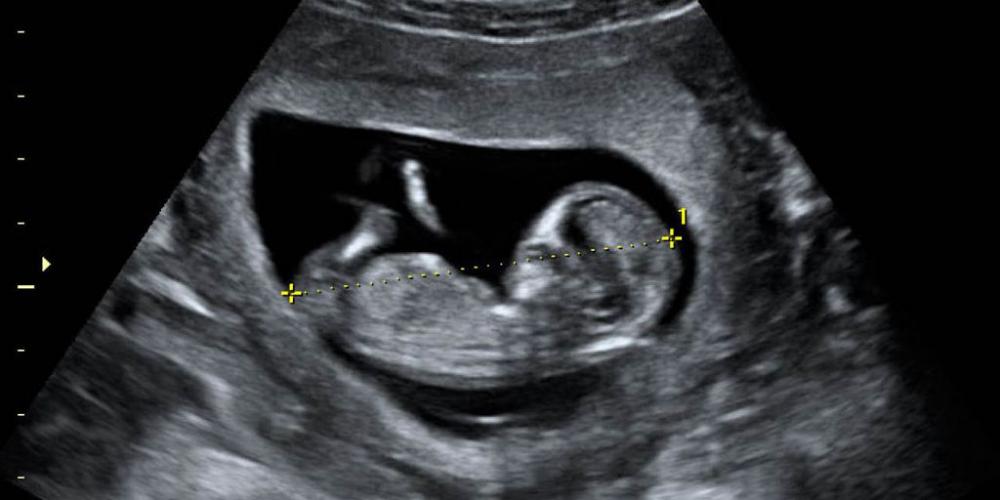

1.000 NIÑOS NACIDOS GRACIAS A LA AYUDA A SUS MADRES

La Red Nacional de Acompañamiento a la Mujer con embarazo vulnerable, que reune a 472 instituciones del país, está cumpliendo 42 meses de un trabajo que ha permitido el nacimiento de 1.000 argentinos. ¨¡Seguimos...